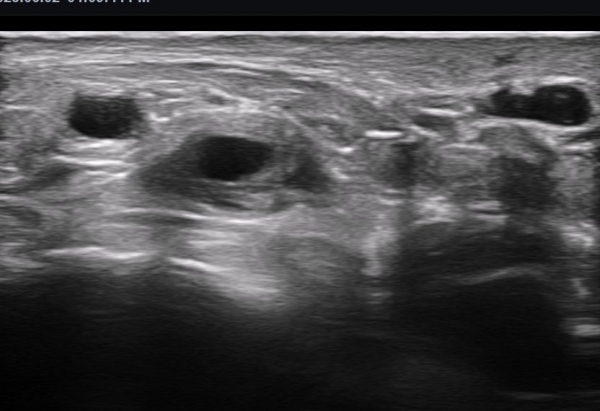

ÃÊÀ½ÆÄ ¼Ò°ß : ºñº¹½Å°æ Ⱦ´Ü¸é°Ë»ç¿¡¼­(»çÁø 1~13) ºñº¹½Å°æÀÇ Àú¿¡ÄÚ ºÎÁ¾°ú ´Üºñ°ñ°Ç³» ³¶Á¾¼º º´º¯ÀÌ °üÂûµÈ´Ù.